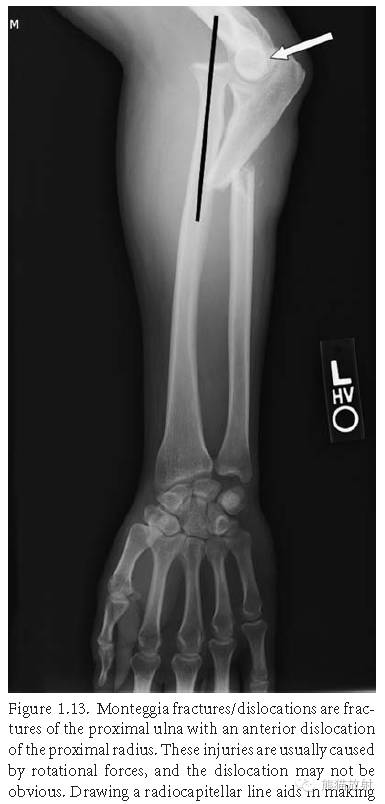

孟氏骨折:尺骨上1/3骨折合并桡骨小头脱位;由旋转暴力所致的损伤,脱位可不明显,桡肱小头线有助于脱位的诊断。